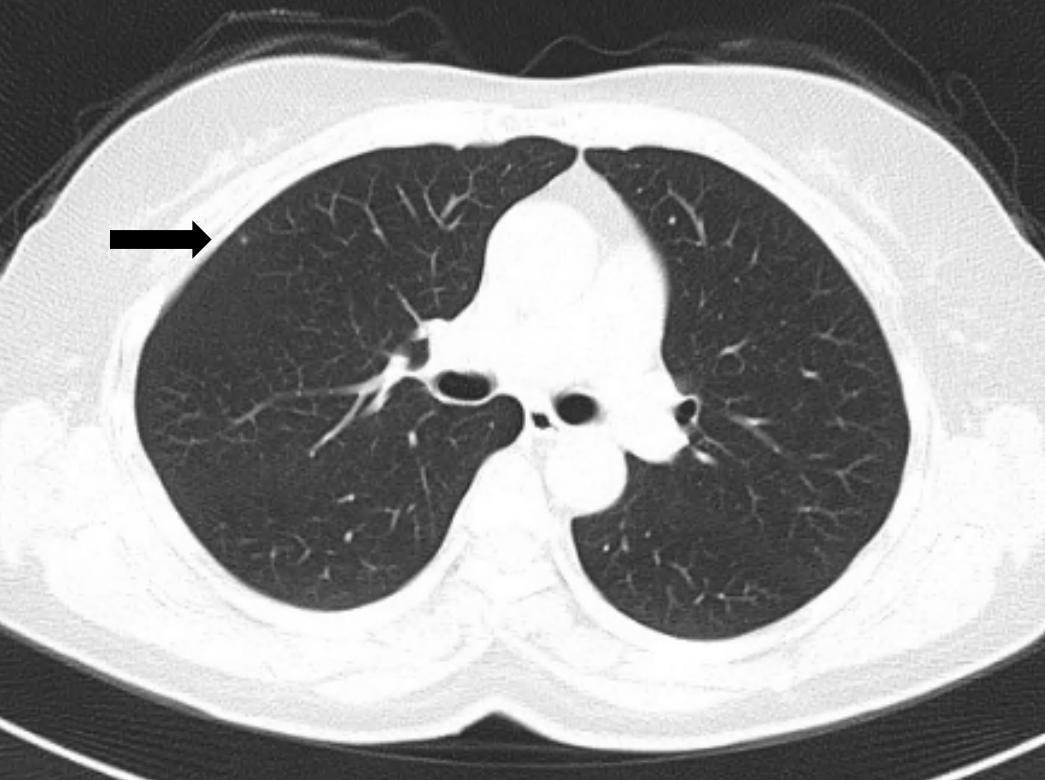

导语:肺结节指的是在胸部CT扫描当中发现的, 圆形、椭圆形、直径不超过三公分的由肺实质包围的肺内病灶。

若肺结节在随访中有以下变化时,多考虑为恶性

1、病灶不断增大,或者是稳定时出现了实质成分;

2、结节直径变大,并且符合了肿瘤的生长规律,逐渐压迫到了附近的器官;

3、血管生成符合恶性结节的一定规律,并且出现了结节增大的现象;

4、病灶在不断缩小并且出现了一定的实质成分,或者是其中的实性成分在增加;

5、肺结节在肺里不断的增大,并且出现了胸膜凹陷等方面的现象,这说明结节在逐渐恶化,一定要及早就医检查。